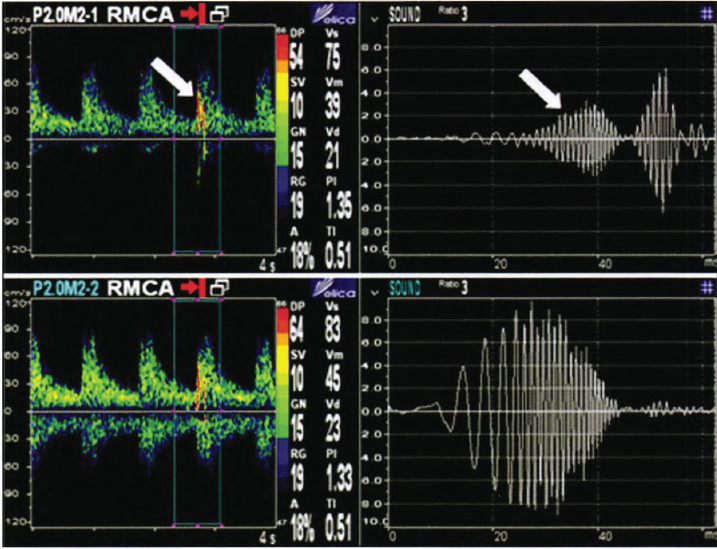

經(jīng)顱多普勒監(jiān)測(cè)MES聲譜圖